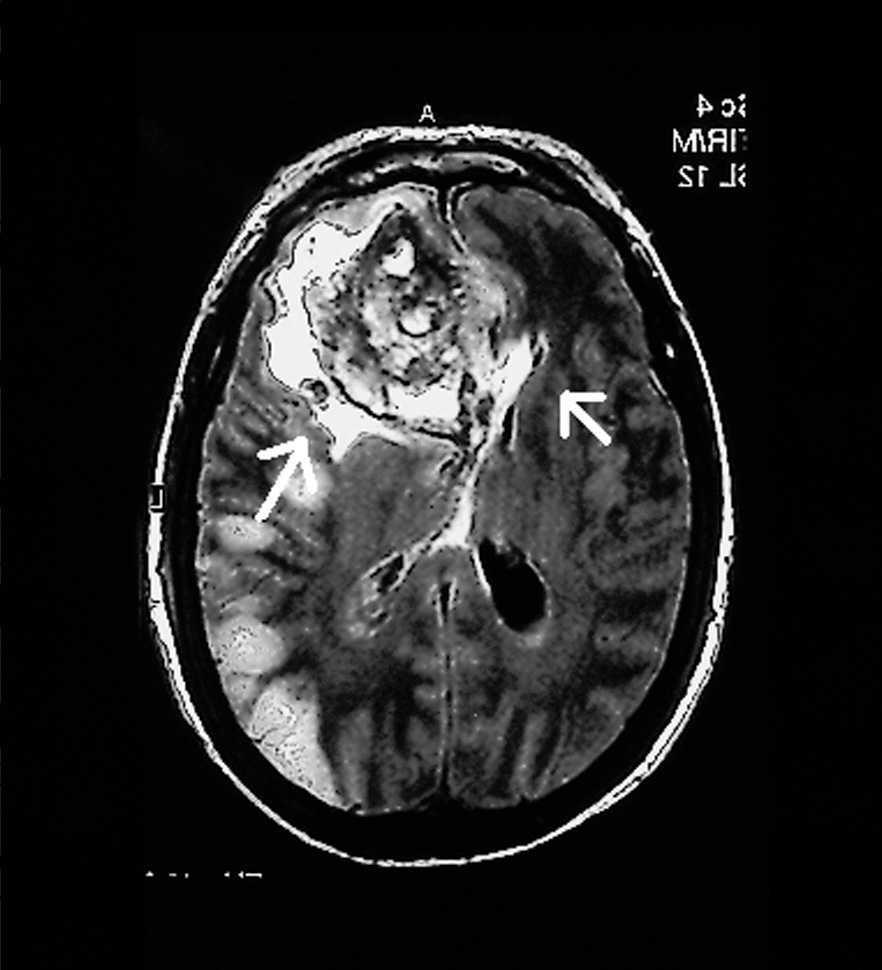

Mujer de 65 años, que ingresó en el Servicio de Medicina Intensiva diagnosticada de meningitis por Streptococcus pyogenes secundaria a otitis supurada y mastoiditis izquierda. Antibioticoterapia según antibiograma. Se realizó tomografía axial computarizada (TAC) por deterioro del nivel de conciencia compatible con meningitis. Tres días después presentó status convulsivo que fue tratado con inducción de coma barbitúrico; se realizó nueva TAC (fig. 1) sugerente de encefalitis necrotizante corticosubcortical temporooccipital izquierda secundaria a vasculitis o a trombosis venosa cortical. El octavo día de ingreso presentó anisocoria, por lo que se le realizó resonancia magnética (RM) (fig. 2) que demostró hematoma frontal izquierdo espontáneo que requirió drenaje quirúrgico. La enferma estaba recibiendo 80 mg/24 h de heparina sódica en perfusión continua por HDFVVC, con tiempos de cefalina en el rango normal. La paciente presentó mala evolución, falleciendo a los 20 días del ingreso tras limitación del esfuerzo terapéutico en el contexto de shock séptico refractario (cultivos necrópsicos en Pseudomonas aeruginosa en pulmón y serosa pleural) y fallo multiorgánico.

Figura 2